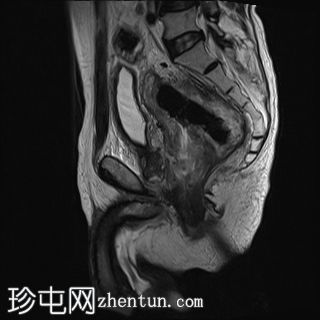

冠状位

T2加权像

直肠下三分之一处可见一段弥漫性不规则肠壁增厚,伴浆膜外延伸,在右前外侧壁形成“C”形肿块,增强后呈不均匀强化,中央可见坏死。

左侧外侧壁和后壁可见大片缺损,内含气体和粪便,被不规则增厚的肠壁包裹。该缺损在T1加权像上呈低信号,在T2加权像上呈高信号,并伴有明显的扩散受限。

可见肠系膜脂肪间隙条索状改变和水肿。